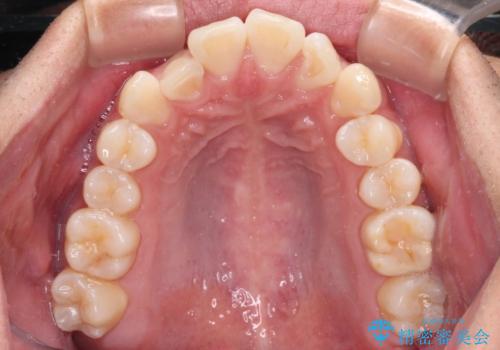

前歯のデコボコをインビザラインで綺麗に改善

- 上下前歯のデコボコとクロスバイトを気にして来院された患者様です。

インビザラインを用い、IPR(歯と歯の間を削る)と歯列全体を拡大させることで、歯並びを整えていくこととしました。

毎日22時間の装着時間を徹底してくださったのですが、左右ともに臼歯が咬合しなくなるという、インビザライン独特の症状が強く長く続いてしまい、終了するまでに長期間を要してしまいました。